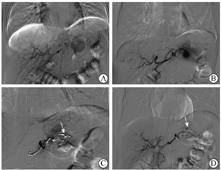

2019年8月7日入院体格检查示体温为36.5 ℃,脉率为78次/min,呼吸频率为20次/min,血压为120/80 mmHg(1 mmHg=0.133 kPa),精神尚可,可自行步入病房,神志清楚,无贫血貌,皮肤、巩膜轻度黄染,浅表淋巴结无肿大,心肺未见明显异常;腹平软,未见胃肠型和蠕动波,未见腹壁静脉曲张,中上腹轻压痛,无反跳痛,未扪及包块,肝脾肋下未扪及,墨菲征阴性,腹部叩诊鼓音,肝肾区无叩击痛,移动性浊音阴性,肠鸣音为4次/min,双下肢无水肿。血常规检查示白细胞计数为3.7×109/L,中性粒细胞占比为0.495,血红蛋白为101 g/L,血细胞比容为31.20%,血小板计数为336×109/L、超敏C反应蛋白为3.89 mg/L;血清淀粉酶为214 U/L。尿常规、粪常规+粪便隐血试验、肝肾功能、血清电解质、凝血功能、肿瘤标志物、甲状腺功能、自身抗体系列、免疫球蛋白G4、人类免疫缺陷病毒、梅毒螺旋体抗体均阴性。2019年8月7日上腹部CT增强扫描检查(图1、图2)提示慢性胰腺炎急性发作、胰腺多发结石,胰体尾部巨大假性囊肿,假性囊肿内脾动脉假性动脉瘤可能,脾囊肿。2019年8月8日磁共振胰胆管造影(magnetic resonance cholangiopancreatography,MRCP)示左右肝管、肝总管、胆总管粗细不均,局部显示不清,但未见扩张,其内未见明显充盈缺损,胰腺体尾部和脾门区见一长径约10 cm的类长圆形异常信号影,T1、T2加权像均呈混杂信号。脾脏外侧及其后方见一囊状水样信号,长径约7 cm。2020年10月13日入院体格检查示腹部有一长约10 cm手术切口,左侧脾窝穿刺引流管在位,引流液较少,腹软,腹部无压痛和反跳痛。血常规检查示白细胞计数为6.8×109/L,血清淀粉酶为196 U/L。假性囊肿引流液李凡他试验弱阳性,乳糜试验阳性,淀粉酶>12 000 U/L。上腹部CT增强扫描检查示慢性胰腺炎腹部术后,术区及其周围改变。

消化内科谭炜主治医师:患者为中年男性,病程较长,以反复发作上腹痛为主要表现,伴腹胀、体重减轻,上腹部CT检查见胰腺实质、胰管内多发结石和胰管扩张等典型慢性胰腺炎表现,故慢性胰腺炎诊断明确。入院前出现的中上腹痛考虑为慢性胰腺炎急性发作。患者有饮酒史30年,折合每日乙醇摄入量为208 g,推测胰腺炎病因为酒精性。上腹部CT增强扫描检查发现胰体尾部巨大假性囊肿内高密度影,囊肿内脾动脉破裂出血可能性大,目前尚无失血性休克、感染等其他表现,请普通外科、放射介入科医师会诊讨论下一步治疗方案。

普通外科汤靓主治医师:患者慢性胰腺炎急性发作诊断明确,有长期大量饮酒史,无高脂血症,无胰腺外伤或手术史,血钙正常,腹部影像学检查未见胰腺分裂等先天性解剖结构异常,考虑胰腺炎病因为酗酒。此次入院上腹部CT检查可见胰腺假性囊肿内一高密度影,考虑脾动脉假性动脉瘤破裂出血,但出血局限于囊内。脾动脉假性动脉瘤是慢性胰腺炎的少见并发症,建议请放射介入科医师行栓塞治疗。

放射介入科董伟华主任医师:脾动脉瘤主要分为真性动脉瘤(占72%)和假性动脉瘤(占13%)[3],后者常见于有腹部外伤或慢性胰腺炎病史的患者[4]。假性动脉瘤破裂引起的急性出血是最致命的并发症,未经治疗的患者死亡率高达90%~100%,即使积极治疗,死亡率仍为12%~50%[5]。该患者应考虑脾动脉假性动脉瘤破裂。上腹部CT检查发现患者假性囊肿与主胰管不相通,故破裂局限于假性囊肿内,未发生呕血、黑便和粪便隐血试验阳性等消化道出血表现,且发现及时,暂未出现明显临床预后不良证据。但考虑该病死亡风险极高,需立即行动脉瘤栓塞术止血。